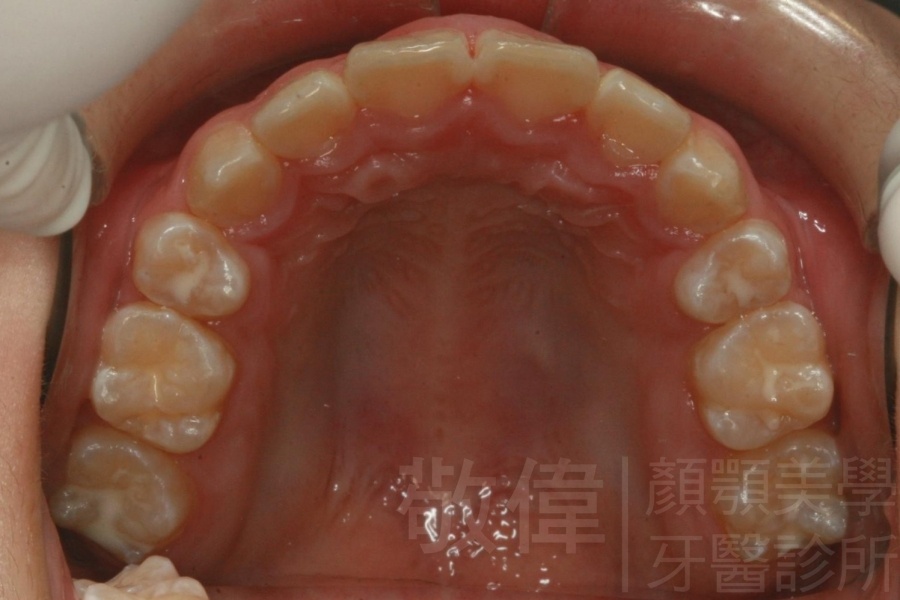

齒顏矯正/上顎暴牙且牙齒極度混亂

矯正前-右   矯正前-正   矯正前-左

矯正前-上   矯正前-下

<個案說明>

上顎暴牙且牙齒極度混亂,經由矯正之後,臉型大幅度改善,牙齒的排列更加的整齊健康。相較於之前眼神充滿精神,自信心展現無遺。